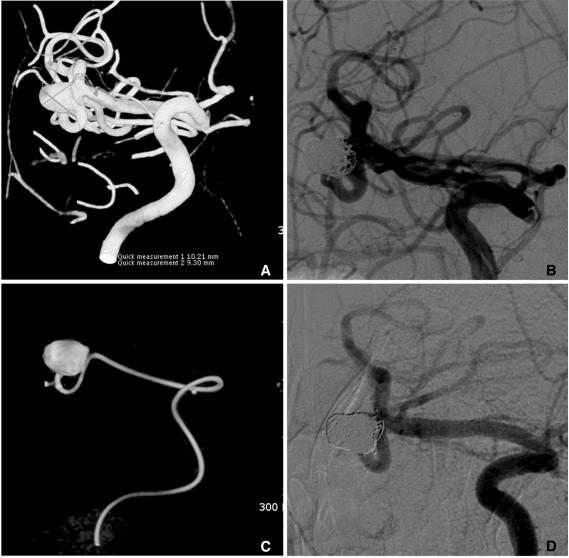

Stent application for the treatment of cerebral aneurysms.

Rapid and striking development in both the techniques and devices make it possible to treat most of cerebral aneurysms endovascularly. Stent has become one of the most important tools in treating difficult aneurysms not feasible for simple coiling. The physical features, the dimensions, and the functional characteristics of the stents show considerable differences. There are also several strategies and tips to treat difficult aneurysms by using stent and coiling. Nevertheless, they require much experience in clinical practice as well as knowledge of the stents to treat cerebral aneurysms safely and effectively. In this report, a brief review of properties of the currently available stents and strategies of their application is presented.

技术和设备的迅速显著发展使得大多数脑动脉瘤能够通过血管内治疗。支架已成为治疗难以单纯栓塞的复杂动脉瘤的最重要工具之一。不同支架的物理特性、尺寸和功能特点存在显著差异。使用支架辅助栓塞治疗复杂动脉瘤也有多种策略和技巧。然而,要安全有效地治疗脑动脉瘤,在临床实践中需要大量经验以及对支架的了解。本报告简要综述了目前可用支架的特性及其应用策略。